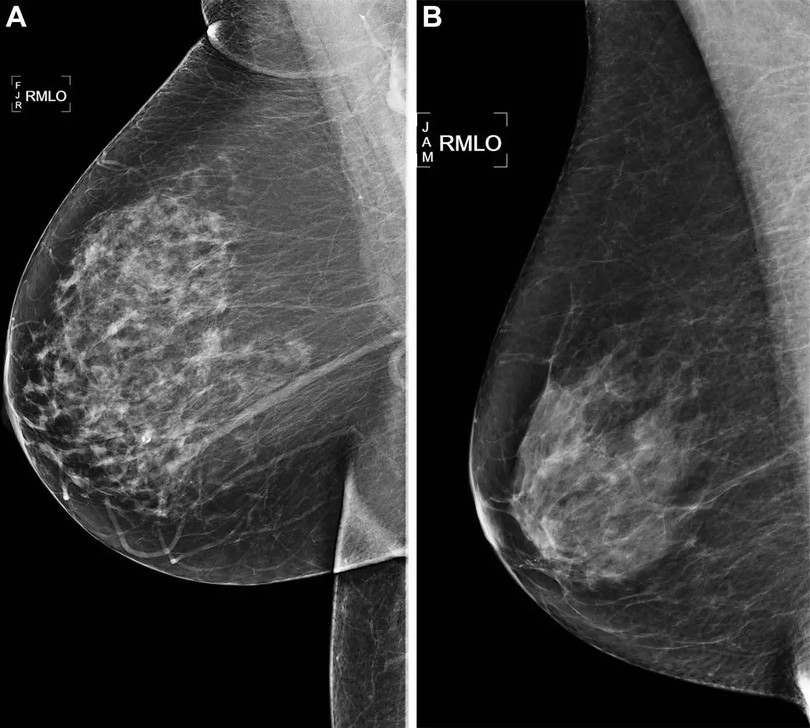

A. Ảnh quang tuyến vú sàng lọc xiên bên phải (RMLO) cho thấy kết quả âm tính từ năm 2016 ở một phụ nữ 73 tuổi có điểm rủi ro, mô hình AI Mirai xác định nguy cơ hơn 90%. Mắc ung thư vú phải năm 2021 sau 5 năm theo dõi. B. Ảnh quang tuyến vú sàng lọc xiên bên phải một phụ nữ 73 tuổi kết quả âm tính, mô hình AI Mirai xác định rủi ro thấp hơn 10%, không phát triển ung thư sau 5 năm theo dõi. Ảnh: Hiệp hội X quang Bắc Mỹ.